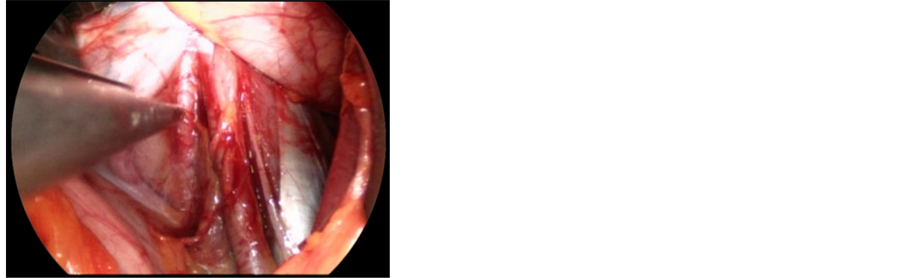

Figure 2. Intraoperative endoscopic view of ureter (indicated with an anatomic claw) and common iliac artery (on the right).

surgical field wide open. Under endoscopic view and magnification, two horizontal cuts are performed with a scalpel on the anterior longitudinal ligament, corresponding to the upper and lower limits of the disc. A vertical incision is then performed on the midline, and the anterior ligament is detached from the midline laterally. This procedure results in two flaps that are preserved to be sutured together after the cage implant. The disc is then removed and the endplates prepared scrapping off the cartilaginous layer (Figure 4). Increasing sizes templates are then implanted in the intervertebral space, in order to find the proper fit (Figure 5). Finally, the definitive cage is implanted and fixed with an anterior plate with screws (we usually implant a three-screw plate for L5-S1 space, and a four-screw plate for the L4-5 disc) in order to increase primary stability (Figure 6). It has been demonstrated that a cage with an anterior plate has the same stiffness than a cage with posterior fixation (four pedicle screws) [3] (Figure 7). The whole procedure is performed through a 5 cm incision with the use of an endoscopic camera. This allows the best view on a HD monitor at a higher magnification for all the surgical steps, allowing a lesser invasivity and a better accuracy.